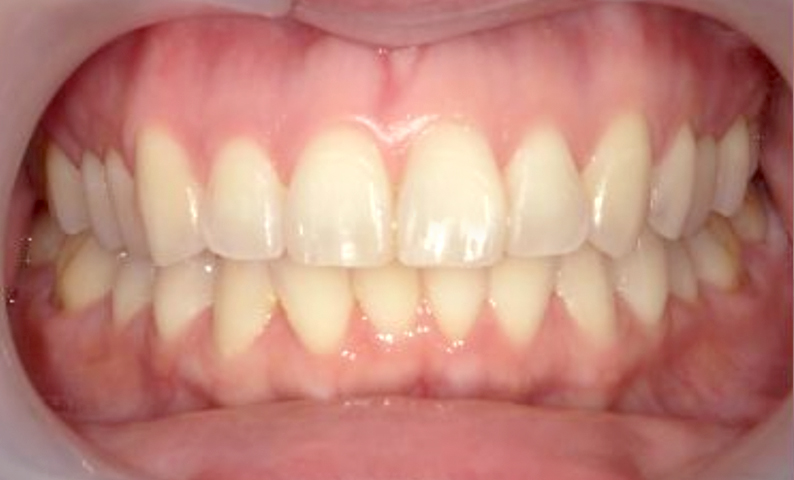

症例_002 前歯「捻転歯」症例

治療期間:10ヶ月金額:54万円+税30代女性少しのねじれ捻転歯前歯の突出感

| Before | After |